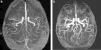

Finalmente, incluimos en este apartado a los hematomas intraparenquimatosos (HIP). Estos presentan cefalea seguida o no de déficits focales, según sea su localización. Si bien generalmente se originan por hipertensión arterial, otras causas menos frecuentes pueden ser el consumo de cocaína, la angiopatía amiloide, las coagulopatías, las malformaciones vasculares y los tumores. Con fines didácticos mostramos un caso de HIP en una paciente con lupus y síndrome de moyamoya9 (fig. 9).

Paciente con cefalea y hematoma en la región tálamo capsular derecha. Se observa (a) en la TC una lesión espontáneamente densa (flecha) y (b) en la secuencia GRE, corte axial, un área de hipointensidad (flecha). (c) La angio-RM tridimensional TOF registra ausencia de señal en los tramos terminales de ambas carótidas internas (puntas de flecha), mientras que (d) en los cortes axiales crudos se identifican pequeños vasos colaterales en las arterias comunicantes posteriores y en ambas arterias cerebrales posteriores, hallazgos correspondientes a enfermedad de moyamoya en estadio III (flechas).